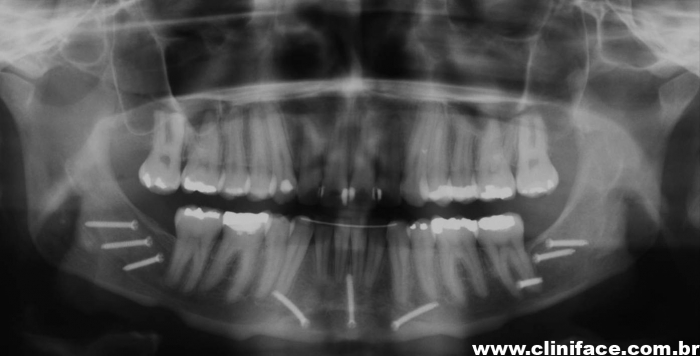

Raio x panorâmico final